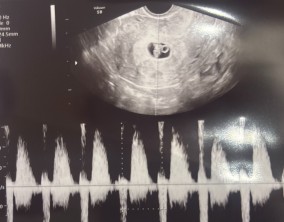

임신 수치 16, 9주차 기적의 기록

서울IVF에서는 단순히 배아 생성과 이식만 해주시는 것이 아니라, 제 생활 전반까지 신경 써주셨습니다. 휴식기에도 그저 기다리는 것이 아니라 항노화에 도움이 되는 링겔을 처방…